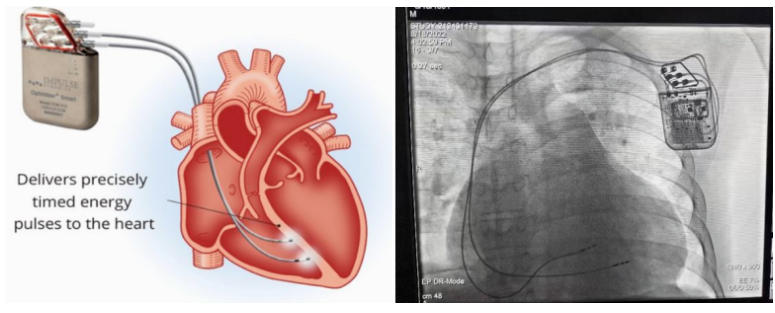

①植入式心臟復(fù)律除顫器

Implantable Cardioverter Defibrillator,ICD

植入式心臟復(fù)律除顫器是一種具有除顫功能的高級起搏器,是一種體積小、能植入患者胸部皮下組織的醫(yī)療設(shè)備。慢性心衰患者易發(fā)生室性心動過速或心室顫動,導(dǎo)致心源性猝死(SCD)。ICD 則能在幾秒內(nèi)自動識別并治療快速室性心律失常,通過低能量心臟轉(zhuǎn)復(fù)和高能量除顫等功能,顯著降低惡性室性心律失常引起的猝死風險??杉皶r自動為患者轉(zhuǎn)復(fù)心律,通俗地說就是裝在體內(nèi)的自動除顫儀。

國內(nèi)研發(fā)企業(yè):無雙醫(yī)療、邁瑞、魚躍、久心、微創(chuàng)、維偉思、麥邦等

②心臟再同步治療

Cardiac Resynchronization Therapy,CRT

心臟再同步化治療,指雙心室起搏器,是通過雙心室同步起搏的方式,幫助心衰患者實現(xiàn)正常起搏的裝置。CRT包括一個口袋大小的脈沖發(fā)生器和三根電極導(dǎo)線,可被植入人體。通過監(jiān)測心律,在發(fā)現(xiàn)異常后,信號發(fā)生器發(fā)送電流脈沖,刺激心室重新同步,從而改善癥狀,提高患者的心臟泵血效率。目前有兩種類型的CRT裝置:植入式心臟再同步治療起搏器(CRT-P)和植入式心臟再同步治療除顫器(CRT-D)。主要區(qū)別在于后者除了改善心臟收縮同步性外,還具備除顫功能,能及時處理危及生命的室性心律失常,避免猝死。

國內(nèi)研發(fā)企業(yè):無雙醫(yī)療、樂普醫(yī)療、先健科技、創(chuàng)領(lǐng)心律、秦明醫(yī)學(xué)等